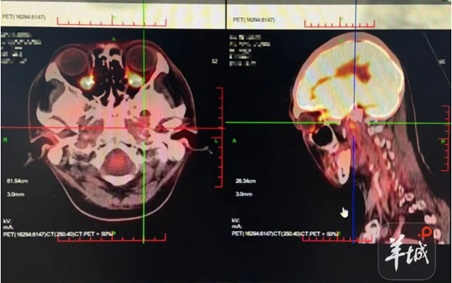

硼中子俘获治疗技术